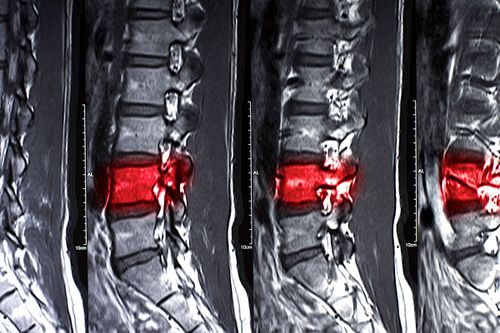

Plusieurs équipes de chercheurs à travers le monde sont sur le point d'accomplir ce qui semblait impossible il y a seulement quelques années... Récemment par exemple, en injectant des cellules souches de moelle osseuse (MSC) chez des patients atteints de lésions de la moelle épinière, des chercheurs de